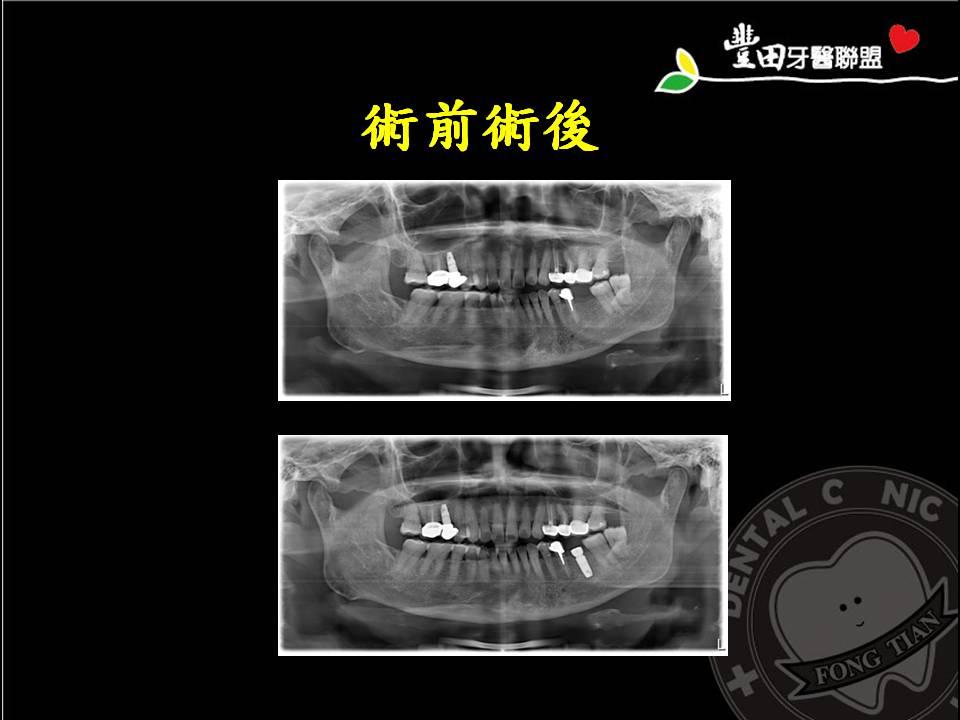

人工植牙

1-2微創植牙 進化版無痛微創植牙